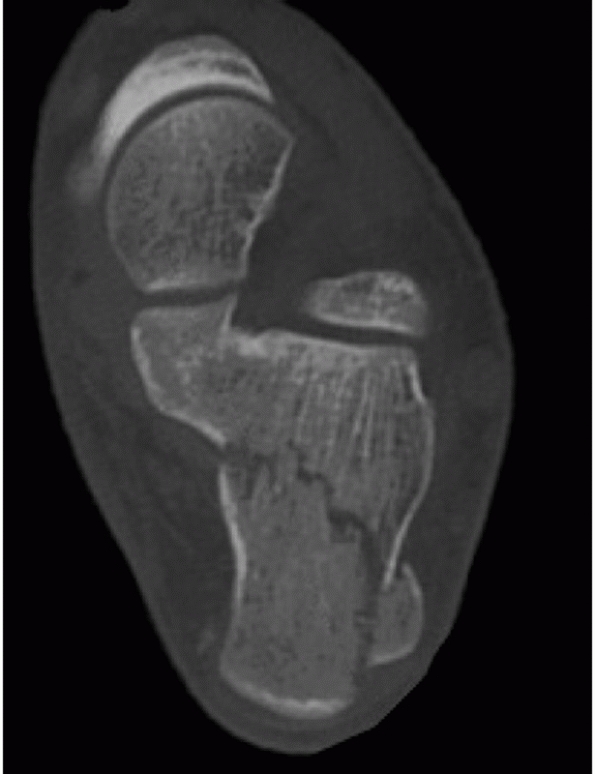

calcaneal fractures and has subsequently allowed for consistent

analysis of treatment results.* CT images are obtained in

the axial, 30-degree semicoronal, and sagittal planes. The coronal

views provide information about the articular surface of the posterior

facet, the sustentaculum, the overall shape of the heel, and the

position of the peroneal and flexor hallucis tendons. The axial views

reveal information about the calcaneocuboid joint, the anteroinferior

aspect of the posterior facet, and the sustentaculum. Sagittal

reconstruction views provide additional information as to the posterior

facet, the calcaneal tuberosity, and the anterior process (Figs. 59-13 and 59-14).